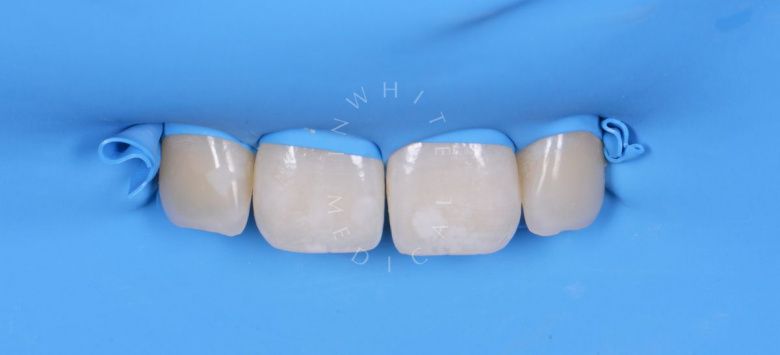

Лечение фиссурного кариеса под увеличением

Стоматология Москва лучшие клиники. Лечение фиссурного кариеса под увеличением - после процедуры